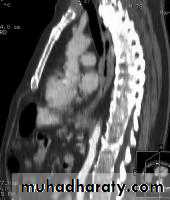

CT finding of esophageal malignancy

1.Eccentric or circumferential wall thickening is greater than 5 mm.

2.Peri-esophageal soft tissue and fat stranding may be demonstrated.

3.A dilated fluid- and debris-filled esophageal lumen is proximal to an obstructing lesion.

4.Aortic invasion .

5.Osophageal CA is often metastatic at the time of presentation ( look for the LN & distal metastasis ) .